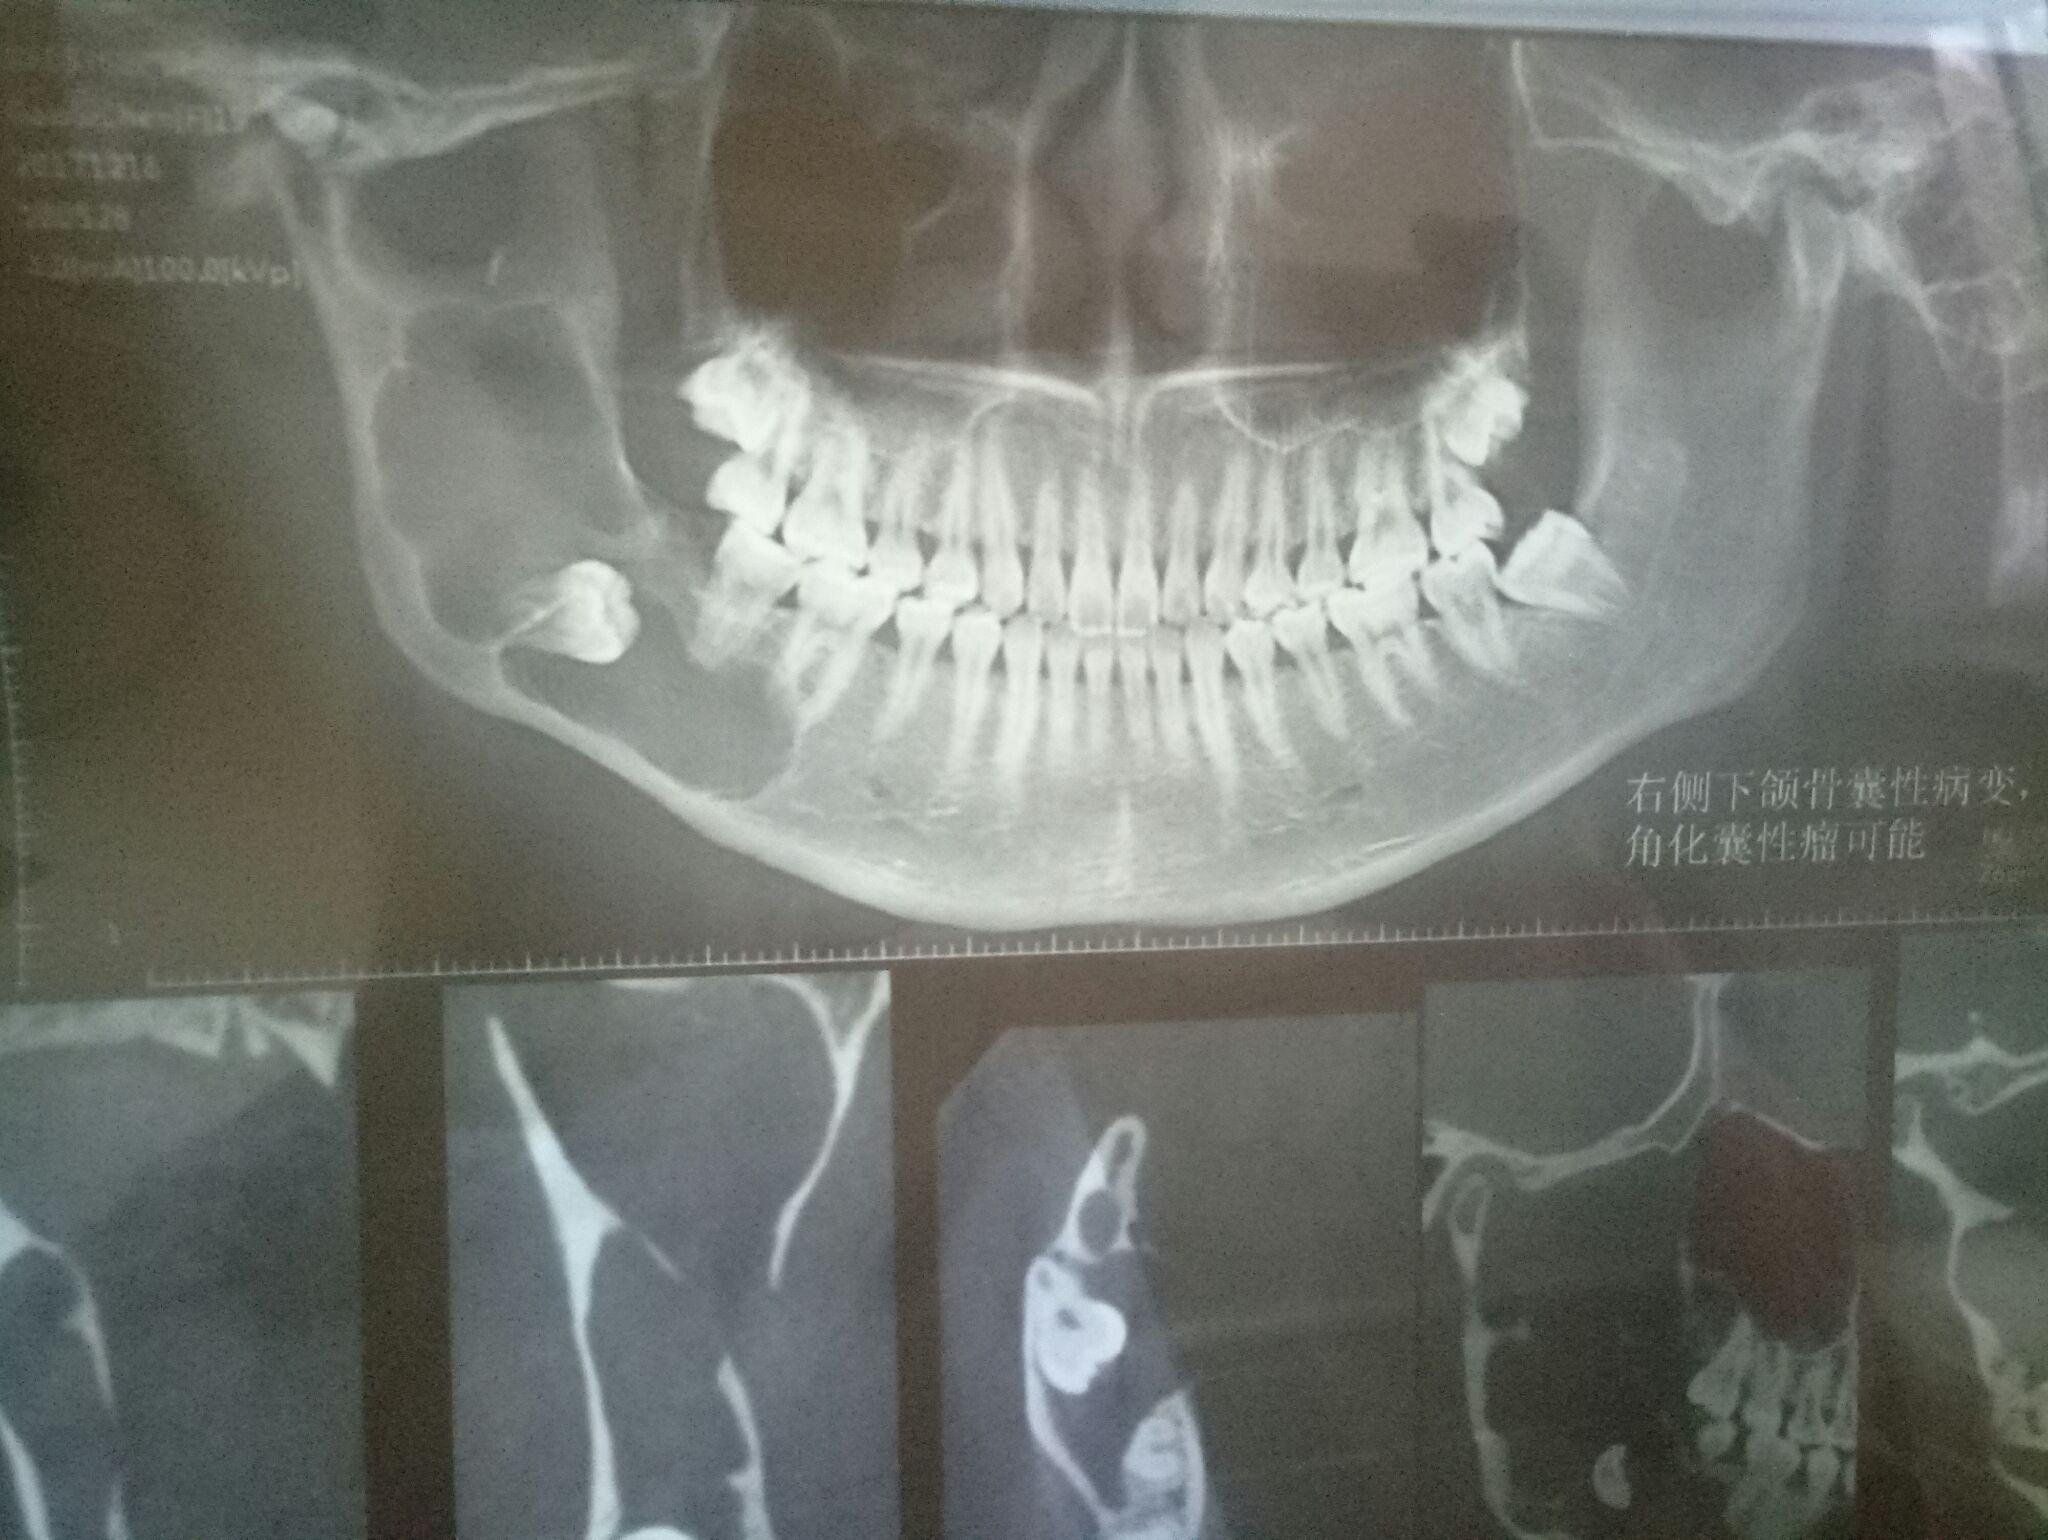

右下颌骨角化囊性瘤

阻生牙下颌骨囊肿xct片请教如何处理